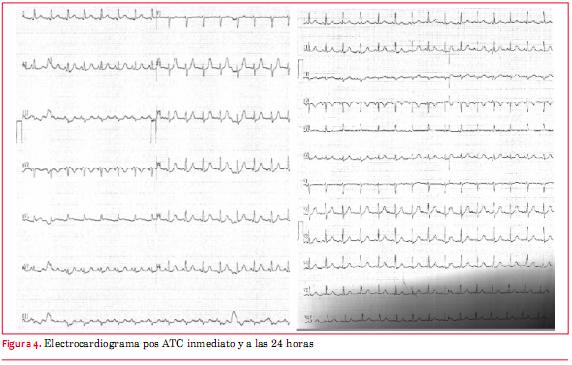

Se realiza angioplastia de arteria circunfleja y primer ramo marginal con stent Promus Premier 3,5 por 28 mm y stent Promus Premier 2,5 por16 mm, respectivamente, con buen resultado angiográfico (figura 3), alivio del dolor y normalización del ECG (figura 4).